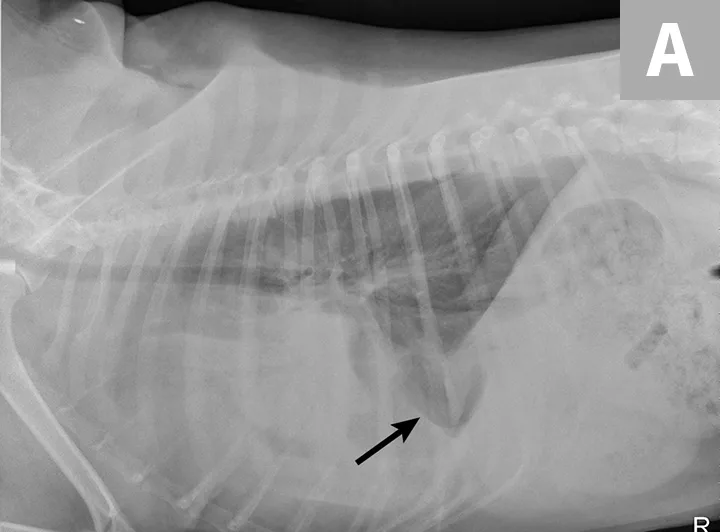

Radiographs obtained after thoracocentesis demonstrated improved pleural effusion and consolidation of the left middle lung lobe (Figure 3). Based on the soft tissue bulge near the hilum and the air bronchocram extending cranially, the primary differential was lung lobe torsion (LLT). Other considerations included pulmonary mass, abscess, or granuloma.

FIGURE 3A

Right lateral (A) and ventrodorsal (B) thoracic radiographs obtained after thoracocentesis showing improvement in pleural effusion with a persistent soft tissue opacity in the left mid-to-cranial thorax. An air bronchogram is seen extending cranially from the hilus (arrowhead) where a subtle bulge (arrow) is present.